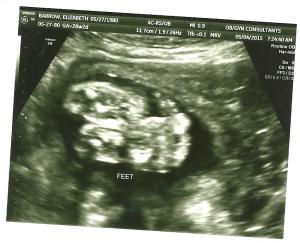

Movement: I actually can see my stomach move now. He has some big kickers! He loves to kick and move. He switched positions this week from sideways to vertical. It was so weird. Now he is back to his feet on my left side and his head on my right. He is sitting really low!

The large kickers!